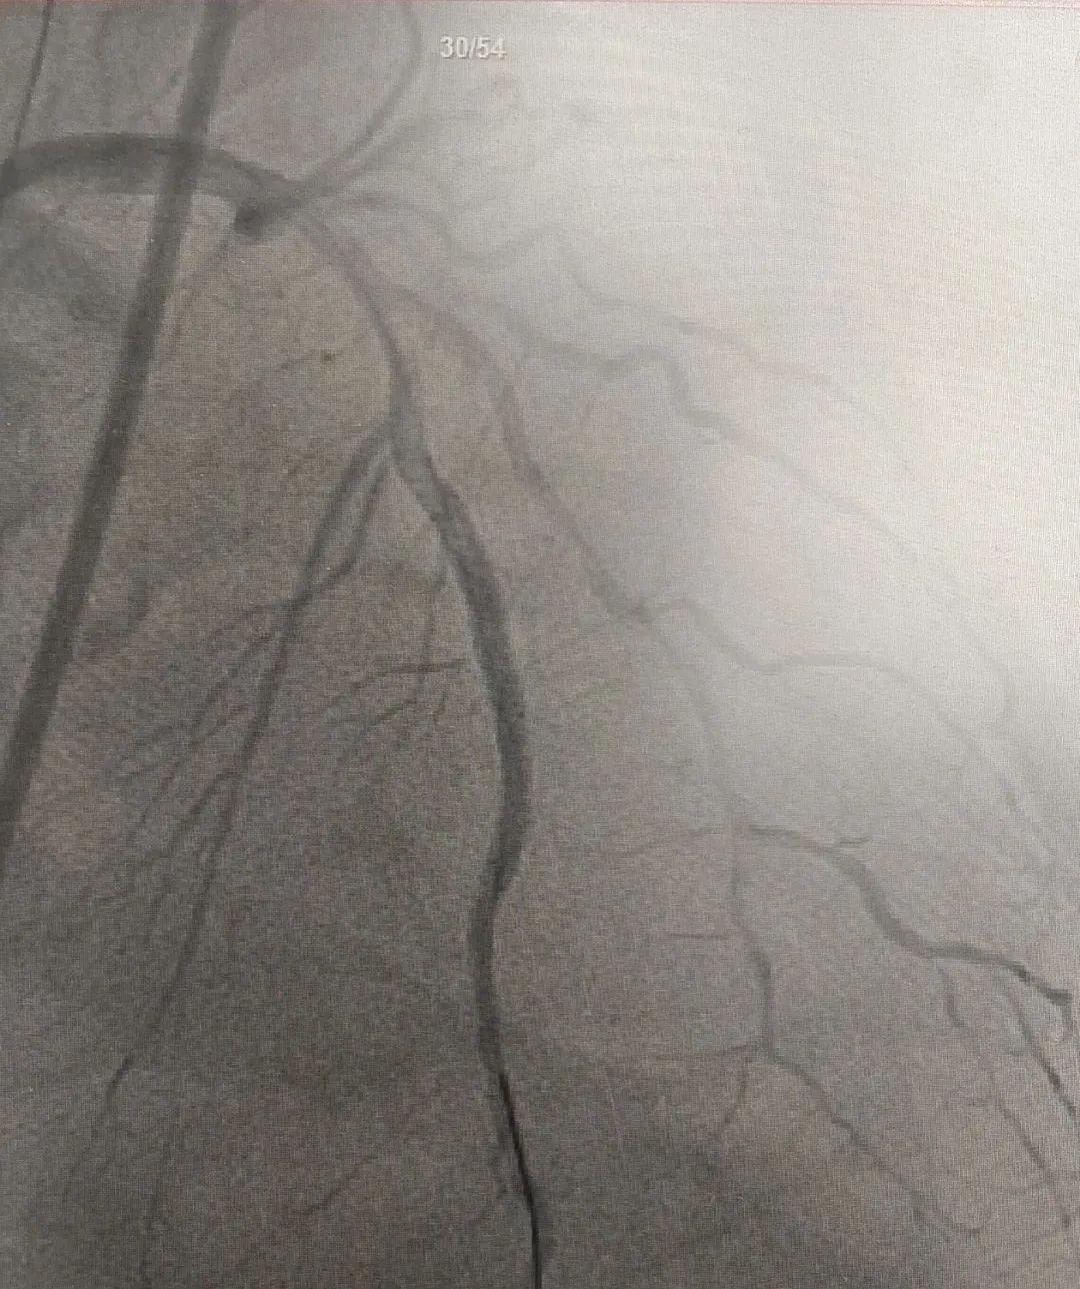

近日,玉山县黄家驷医院(玉山县人民医院)医护团队和玉山县博爱医院医护人员共同上演了一场“生命接力赛”,经过近7小时的救治,成功抢救一名呼吸心脏骤停、急性心肌梗死的重症患者。

10月17日,家住玉山县的何先生因胸闷气憋入住玉山县博爱医院,然而,在就诊过程中突发呼吸心跳骤停……医护人员立即予以心肺复苏、气管插管、电除颤等急救措施直至患者恢复自主心率,但意识仍丧失。考虑到患者病情危重,博爱医院医护团队与患者家属沟通后,即刻转至玉山县黄家驷医院(玉山县人民医院)继续救治。

发生急性心肌梗死,要采取就近抢救原则,及早送至有经皮冠状动脉介入治疗(PCI)能力的医院行PCI治疗,如就诊医院无法行PCI治疗,建议立即转至附近有PCI能力医院行PCI治疗或溶栓治疗,尽量缩短发病时间至开通闭塞血管的总缺血时间,总缺血时间越短,患者的生存率及康复率就越高。

我院胸痛中心为胸痛患者24小时开通生命“绿色通道”,早发现早诊断早治疗,能争分夺秒为患者开通闭塞血管,挽救濒死的心肌,缩小梗死的面积,保护心脏功能,及时处理心肌梗死的各种并发症,是玉山及周边地区心梗患者救治的较佳选择。

自 2021 年 4 月我院启动胸痛中心建设以来,全院上下高度重视、全员动员,有序地推进各项工作的开展,胸痛中心建设工作不断完善,于2023年8月通过国家级胸痛中心认证,成为国家级胸痛中心的一员。这标志着我院对急性心肌梗死等高危胸痛的救治水平、流程优化、硬件设施等方面均已达到国家级标准。

在推进胸痛中心建设中,我院严格做好有指征的筛查工作,就诊的病人在增加,冠脉介入术数量在增加,介入自主完成率也越来越高(急性心梗介入手术自主完成率达100%),心梗患者在本地发现率、救治率均明显提升,获得了明显的社会效益。在全市的排名中:2024上半年,急性心梗收治100例,冠脉介入手术120例,两项均位列全市第二名,仅次于上饶市人民医院,已领先于同级县医院。